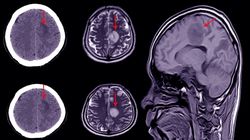

Witam serdecznie. Krótki opis mojego przypadku: od kilku lat bóle głowy lewego ucha, połowy twarzy, szyi z lewej strony, zawroty głowy. Wykonano badanie MR piramid kości skroniowych: Poniżej nerwu VII i VIII na poziomie zbiorników kątów mostowo - móżdżkowych obustronnie drobne, pasmowate wzmocnienie sygnału, grubości do 3 mm, przebiegające w kierunku otworów Luschki - najpewniej nieco poszerzone sploty naczyniówkowe na wysokości zachyłków bocznych komory IV. Proszę o interpretację wyniku.